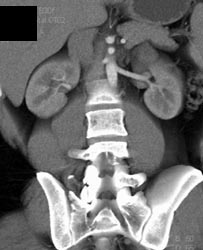

Hypervascular Renal Cell Carcinoma